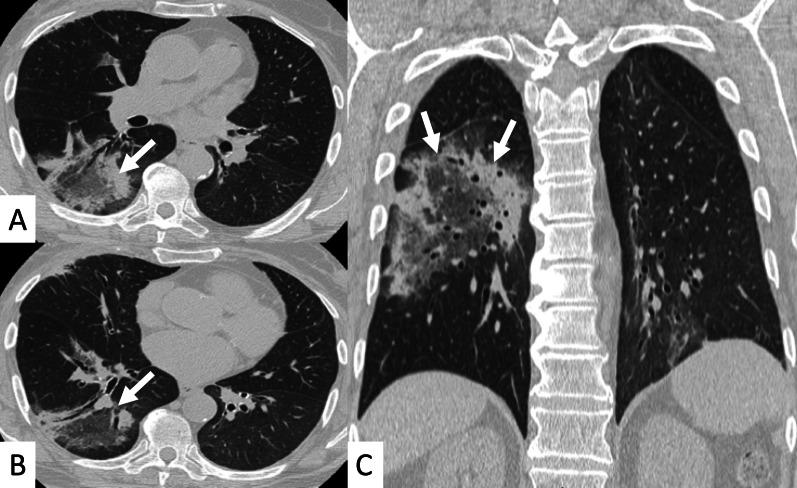

Connective tissue diseases (CTDs) include a spectrum of disorders that affect the connective tissue of the human body; they include autoimmune disorders characterized by immune-mediated chronic inflammation and the development of fibrosis. Lung involvement can be misdiagnosed, since pulmonary alterations preceded osteo-articular manifestations only in 20% of cases and they have no clear clinical findings in the early phases. All pulmonary structures may be interested: pulmonary interstitium, airways, pleura and respiratory muscles. Among these autoimmune disorders, rheumatoid arthritis (RA) is characterized by usual interstitial pneumonia (UIP), pulmonary nodules and airway disease with air-trapping, whereas non-specific interstitial pneumonia (NSIP), pulmonary hypertension and esophageal dilatation are frequently revealed in systemic sclerosis (SSc). NSIP and organizing pneumonia (OP) may be found in patients having polymyositis (PM) and dermatomyositis (DM); in some cases, perilobular consolidations and reverse halo-sign areas may be observed. Systemic lupus erythematosus (SLE) is characterized by serositis, acute lupus pneumonitis and alveolar hemorrhage. In the Sjögren syndrome (SS), the most frequent pattern encountered on HRCT images is represented by NSIP; UIP and lymphocytic interstitial pneumonia (LIP) are reported with a lower frequency. Finally, fibrotic NSIP may be the interstitial disease observed in patients having mixed connective tissue diseases (MCTD). This pictorial review therefore aims to provide clinical features and imaging findings associated with autoimmune CTDs, in order to help radiologists, pneumologists and rheumatologists in their diagnoses and management.

结缔组织病(CTDs)包括一系列影响人体结缔组织的疾病;它们包括以免疫介导的慢性炎症和纤维化发展为特征的自身免疫性疾病。肺部受累可能会被误诊,因为肺部改变仅在20%的病例中先于骨关节炎表现出现,且在早期阶段没有明确的临床发现。所有肺部结构都可能受累:肺间质、气道、胸膜和呼吸肌。在这些自身免疫性疾病中,类风湿关节炎(RA)的特征是普通型间质性肺炎(UIP)、肺结节和伴有空气潴留的气道疾病,而系统性硬化症(SSc)常表现为非特异性间质性肺炎(NSIP)、肺动脉高压和食管扩张。NSIP和机化性肺炎(OP)可见于多发性肌炎(PM)和皮肌炎(DM)患者;在某些情况下,可观察到小叶周围实变和反晕征区域。系统性红斑狼疮(SLE)的特征是浆膜炎、急性狼疮性肺炎和肺泡出血。在干燥综合征(SS)中,HRCT图像上最常见的表现是NSIP;UIP和淋巴细胞间质性肺炎(LIP)的报道频率较低。最后,纤维化NSIP可能是混合性结缔组织病(MCTD)患者中观察到的间质性疾病。因此,本图像综述旨在提供与自身免疫性CTDs相关的临床特征和影像学表现,以帮助放射科医生、呼吸科医生和风湿病科医生进行诊断和管理。